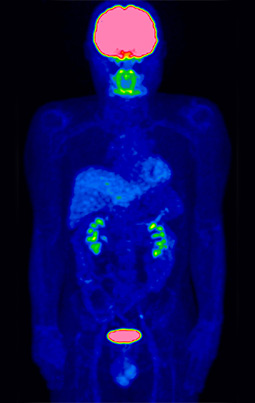

④がんの進行度、転移・再発の有無を確認できます

がんの恐いところは、離れた臓器に転移したり、治療しても再発してくる場合があることです。

しかもがんの転移や再発がどの臓器に出現するかを予測することは大変困難です。

一度の検査で全身をみることができるFDG-PET検査は、がんがどの程度まで拡がっているかといった、がんのステージを判断(病期診断)したり、思わぬ場所への転移や再発がないかどうかを調べるのに役立ちます。

これらを確認することは、その後の治療方法を決めるのにとても重要です。

PET検査による病状の把握で治療方針が変わることも少なくありません。